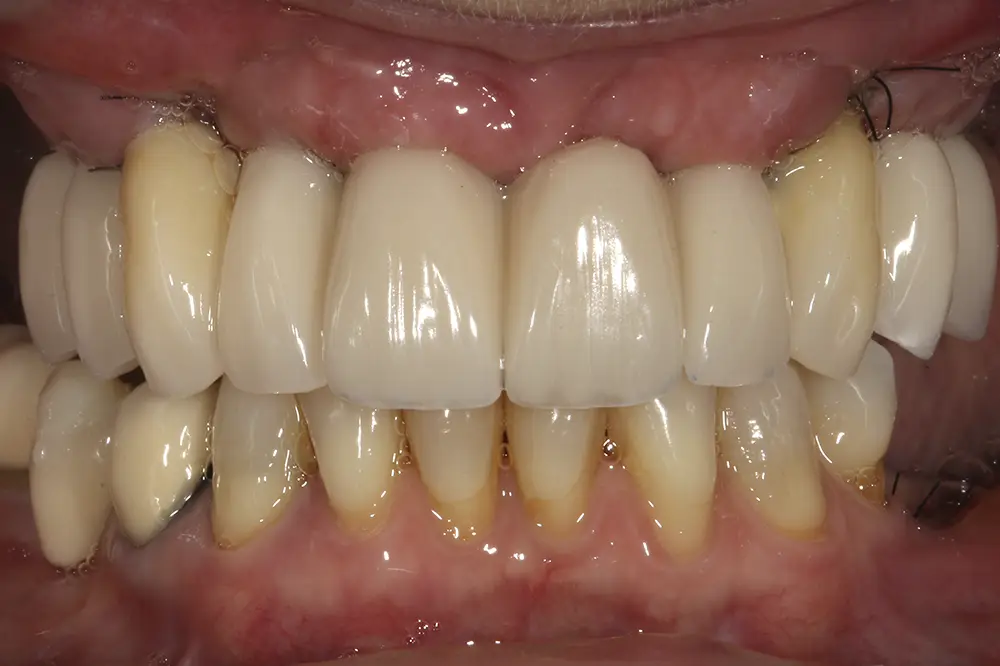

Para los sectores posteriores, se fabricaron estructuras mediante fresado CAD/CAM del mismo modo que la barra anteriormente descrita, con la diferencia de que sobre ellas se colocó un recubrimiento de cerámica (figs. 47-49). La paciente continúa en seguimiento, sin evidenciarse pérdidas óseas significativas en ninguno de los implantes estrechos y cortos que conforman la restauración de todo el maxilar superior tras tres años de carga de la prótesis definitiva (y hasta 4,5 de la carga de los implantes de la fase inicial de carga inmediata) (fig. 50).

Figs. 47 y 48. Prótesis terminadas, colocadas en la paciente.